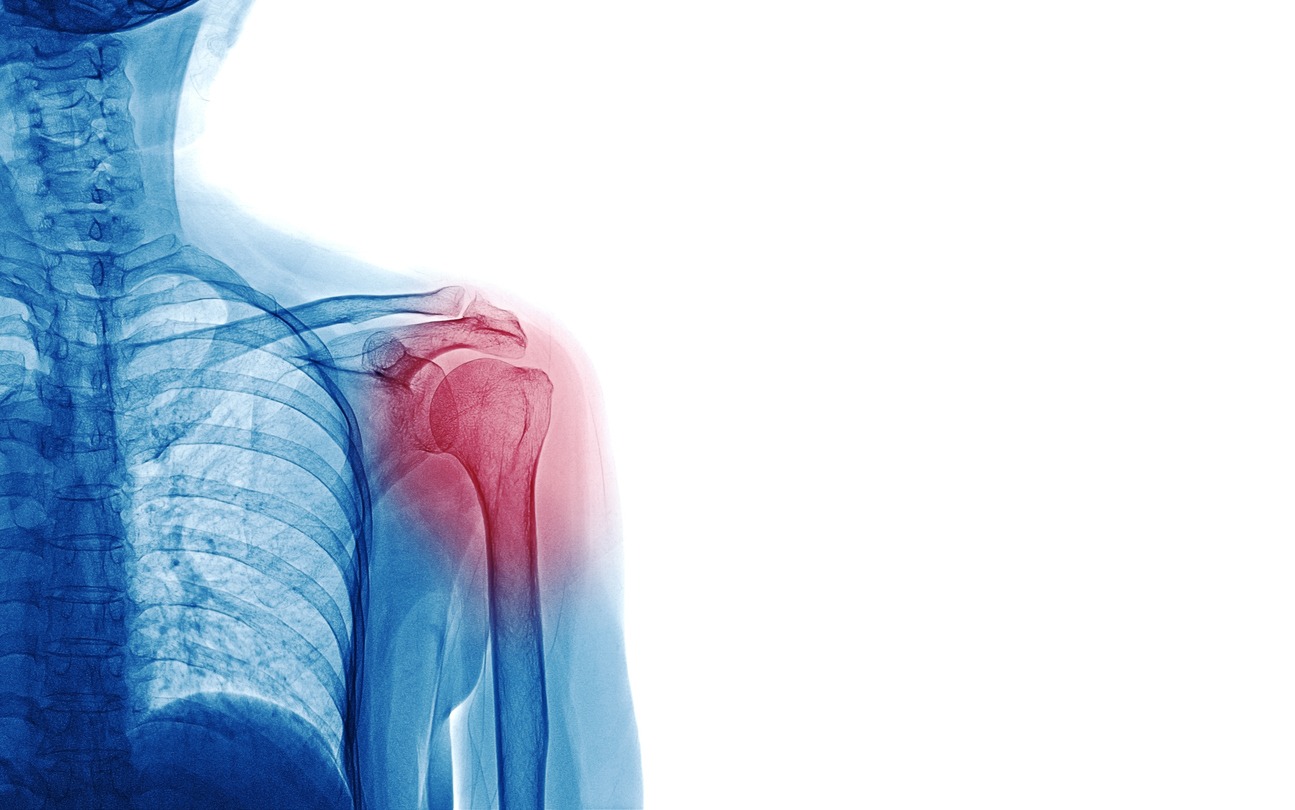

If you’re an athlete, chances are you’re relying heavily on your shoulder to play. Whether you hit, throw, swing, lift, or press – the shoulder and its joints always come into play. The shoulder is one of the most complex joints in the body, giving athletes both mobility and stability. However, that’s hard to balance as the more mobile the shoulder joint is, the less stable it is, and vice versa. The extreme stress, repeated movements, and sheer force are often too much for the shoulders to handle.

Athletes may injure their shoulders, which limits arm movement causing aches and discomfort. In this article, learn about the causes of shoulder pains in athletes, how to treat them, and the exercises you can do to relieve shoulder aches and pains.

Causes of Shoulder Pain

Shoulder pain can develop from problems on any part of the shoulder. Diagnosing the cause and type of shoulder problem is important so you can apply proper treatment. Here are some of the causes of shoulder pain: